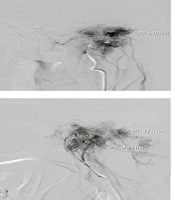

Vascular Blush Size Reduction, Technical Success and Safety of Intra-Arterial Embolization for Glomus Jugular Tumors: A Retrospective Cohort Study

Safeen Rasul Ali,

Ali Kouhi,

Sara Hassani,

Madjid Shakiba,

Jayran ZebardastORCID,

Hossein GhanaatiORCID*

|

Final Published